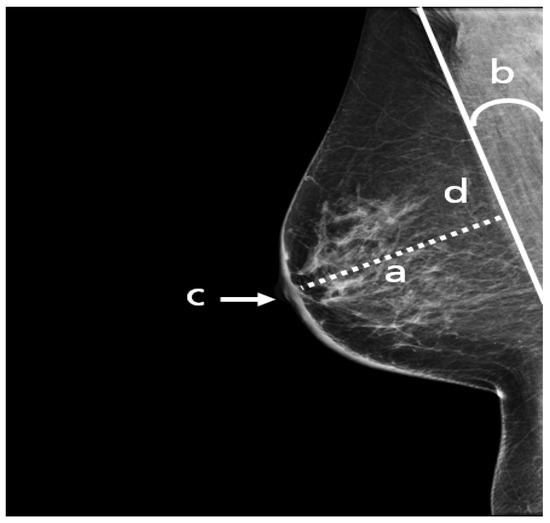

The following points have to be fulfilled in an adequate CC view (Figure 7): the nipple should be in profile, ideally centered (a) or pointing no more than 20° laterally or medially. All breast quadrants must be adequately visualized and the retroglandular fat (b), a fatty tissue closest to the chest wall and appearing as a dark stripe, must be present. The mammograms should not show skin fold obscuring diagnostically relevant parts of the glandular tissue.

Figure 7. An adequate CC view with (a) nipple in profile and centered, (b) visualized retroglandular fat.